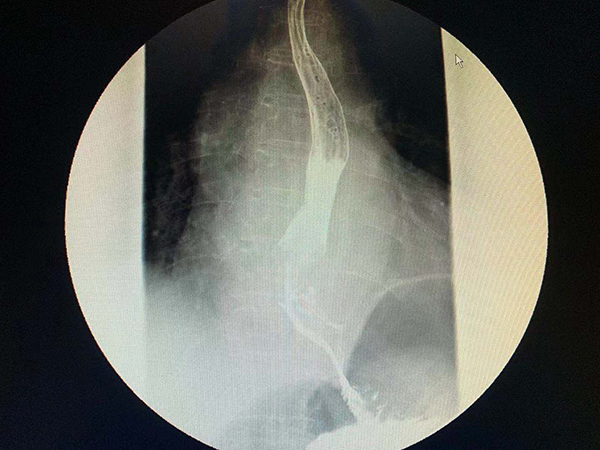

黃淮網(wǎng)  近日,一例81歲老人因進食困難在地方醫(yī)院檢查發(fā)現(xiàn)為食管癌,同時還發(fā)現(xiàn)肺上還有一病灶,性質(zhì)不能確定,因病情復(fù)雜慕名來到徐醫(yī)附院就診。

徐醫(yī)附院胸心外科主任王國祥接診后,仔細(xì)分析發(fā)現(xiàn)肺部病灶也是肺癌,同樣需要切除。患者家屬積極要求同期手術(shù)根治肺和食管兩個癌腫。但患者年事已高,又有冠心病PTCA病史,常規(guī)手術(shù)創(chuàng)傷太大、風(fēng)險高。胸心外科通過網(wǎng)絡(luò)會診,吸取國內(nèi)頂級醫(yī)院的建議,決定利用本院新引進的神器——達(dá)芬奇機器人,在機器人胸腔鏡輔助下,用微創(chuàng)的辦法同期根治兩種病變。

11月14日,在麻醉科手術(shù)室的通力配合下,王國祥主任團隊首先利用機器人的熒光輔助功能精準(zhǔn)切除老人肺癌所在的肺段及腫瘤并最大限度保留老人的正常肺組織,接下來在機器人的輔助下,通過幾個小孔分別切除食管癌、清掃區(qū)域淋巴結(jié),游離病人的胃、并將它提到頸部,在頸部與食管吻合以重建消化道。通過4個小時的努力,成功而安全的完成手術(shù)。